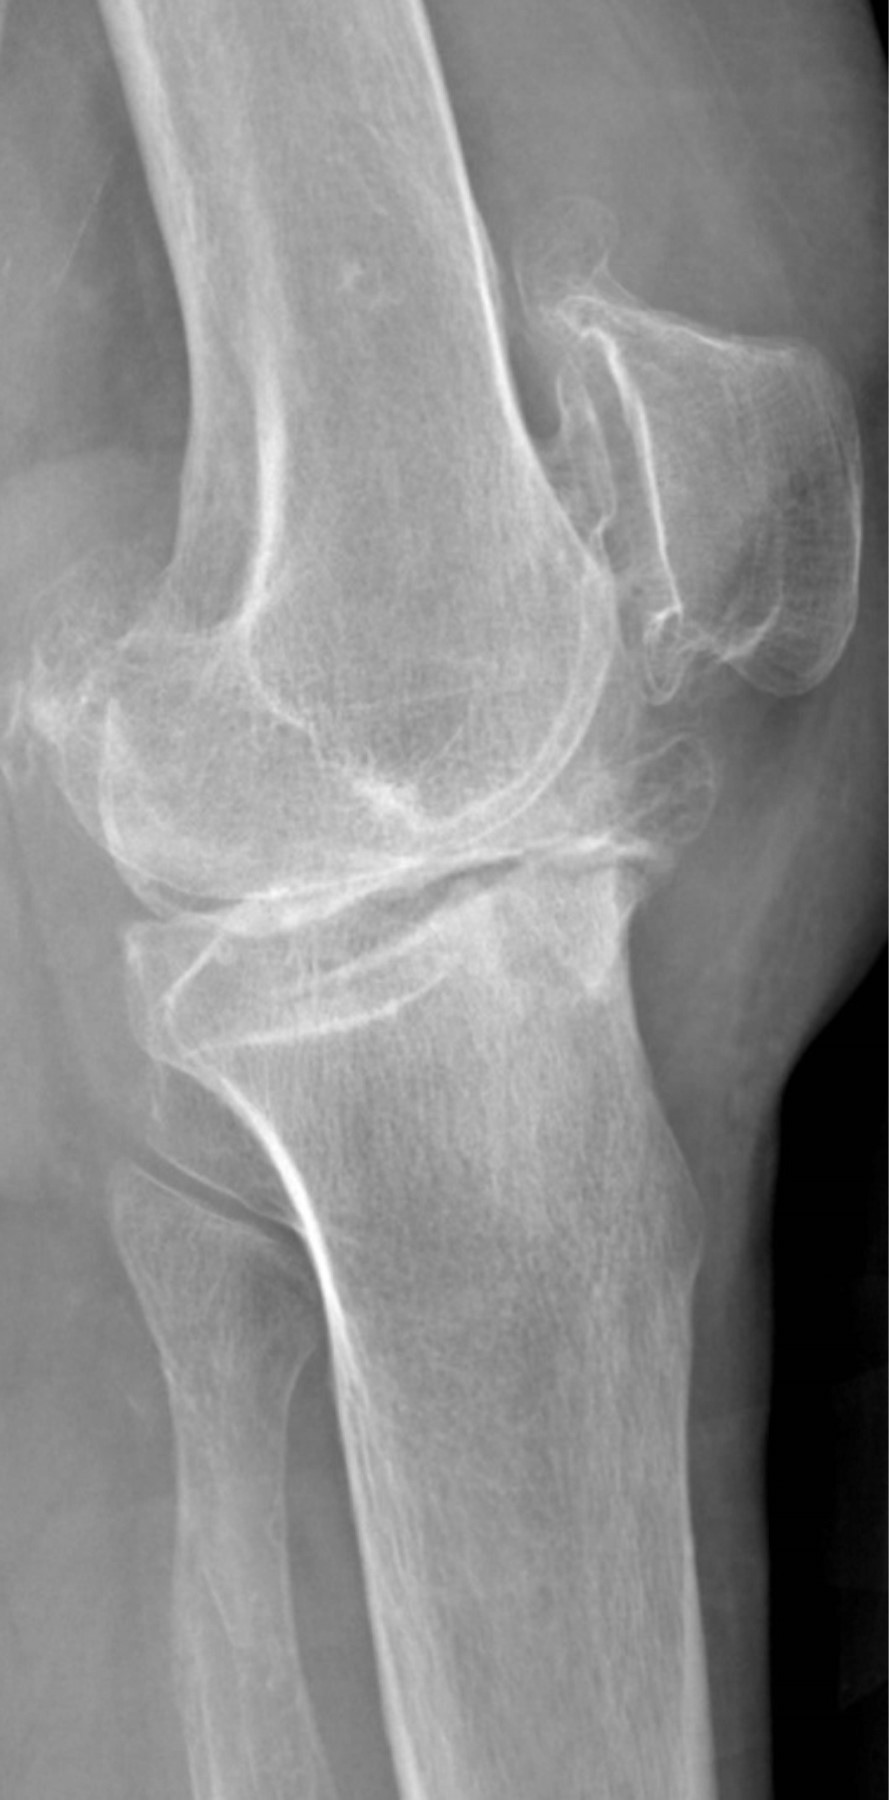

Se presenta caso de mujer de 62 años, dedicada al cuidado del hogar, con antecedente de presbiacusia, la cual acude a consulta externa por gonalgia bilateral, de predominio izquierdo, de siete años de evolución. A la exploración física se aprecia franca deformidad en varo en ambas rodillas (Figura 1), de mayor magnitud en lado izquierdo, con marcha independiente asistida con bastón, rango de movilidad activo con extensión de -5o, flexión de 85o, Ficat y cepillos positivos, cajones negativos y bostezo medial positivo, con limitación por dolor para las actividades de la vida diaria y dolor en EVA de 8. Se solicitan y revisan radiografías anteroposterior (Figura 2) y lateral (Figura 3) de ambas rodillas en bipedestación, encontrando gonartrosis bilateral Kellgreen & Lawrence IV, con defecto tibial medial en rodilla izquierda, por lo cual se le propone tratamiento quirúrgico con artroplastia total de rodilla izquierda posteroestabilizada, debido a la mayor sintomatología en dicho lado.